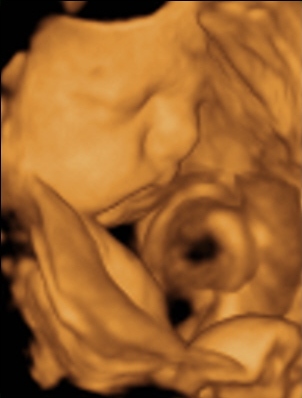

Ma tehát megjártuk a 4D-t meg a cipőboltot. 1,5 órát UHzott a csaj, mert Drága Kistesó nem akarta mutatni magát. Már tornáztam, ettem, ittam épp csak háztömböt nem mentem futni... A végén sikerült 1-2 jobb képet csinálni (azt is csak profilból). Súlya 2 kg (1900valamennyi), mindene 32 hetesnek megfelelő. Minden a helyén van és megvan, hosszú haja van és már most zsíros a Drágám.

No és képek: